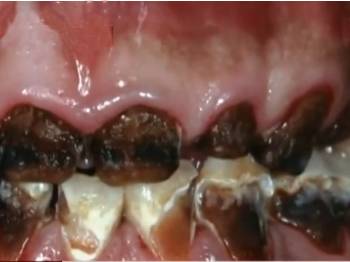

8月16日下午,医院接诊了一个小男孩。妈妈牵着孩子的手,来到了口腔科,华华一张开嘴,在场的所有医生护士全部惊呆了。

最恐怖的是,这个孩子嘴里光秃秃的,几乎看不到牙齿!

华华一共20颗牙,8颗牙烂的只剩下牙根,而且牙根现在全部变成了黑色。还有6颗牙都是齐根断了,孩子现在吃饭已经是个大问题了,根本无法咀嚼食物。

医生说道,华华这个病用专业术语来讲的话,称为“可乐牙”。